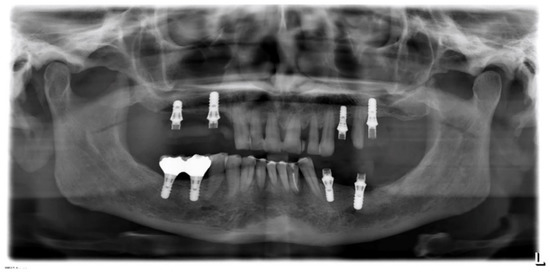

Figure 16. Case 3. Panorex.

A 59-year-old female attended a consultation complaining of aesthetic dissatisfaction with the diastemas between her upper frontal teeth and difficulty speaking and chewing. The patient wore provisional crowns supported by implants in the posterior regions (Figure 15). After an accurate diagnostic phase, which involved (1) intra-oral radiographic status, (2) probing of natural elements and implants, and (3) mobility and occlusal evaluation, the patient was classified as affected by periodontitis of stage 4 (Figure 16). Strong occlusal contacts were detected between upper and lower incisors, suggesting that occlusal trauma could contribute to the severity of the incisors’ mobility. In this regard, the provisional posterior crowns were maintaining the previous (reduced) vertical dimension without mitigating anterior contacts.